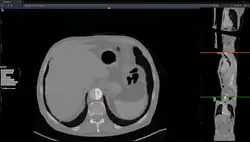

Aortic Dissection Inpainting under Studierfenster.

Other features of Studierfenster are the automatic cranial implant design with a neural network,[9][10] the inpainting of aortic dissections[11] with a generative adversarial network,[12][13] an automatic aortic landmark detection with deep learning[14] in computed tomography angiography scans, and a GrowCut algorithm implementation for image segmentation.